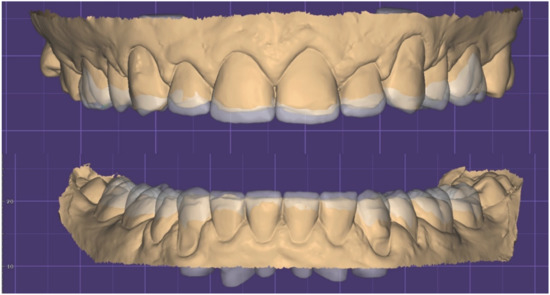

2.1. Planning Phase

2.2. Restorative Phase